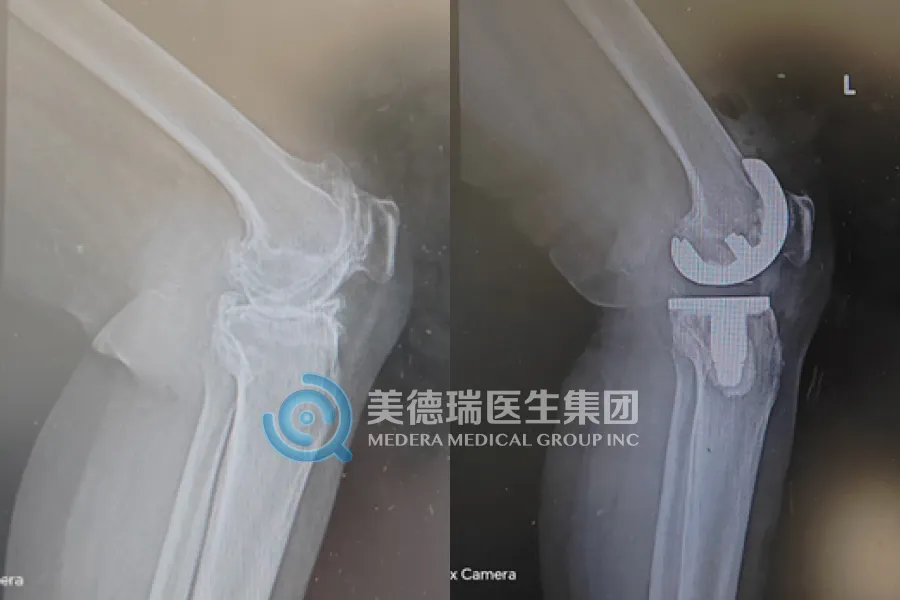

近期,该中心已常态化开展包括膝关节置换、人工股骨头置换、关节镜下半月板缝合、腰椎融合及椎板减压术等在内的多项核心术式,覆盖了关节、脊柱、运动医学等多个领域,标志着中心已从单纯的“技术引入”迈向了“能力扎根”的全新阶段,区域骨科诊疗水平实现了实质性的飞跃。

- 对于备受膝关节炎折磨的老人,人工膝关节置换术能有效缓解疼痛,显著改善关节功能,让他们重新享受行走的自由。